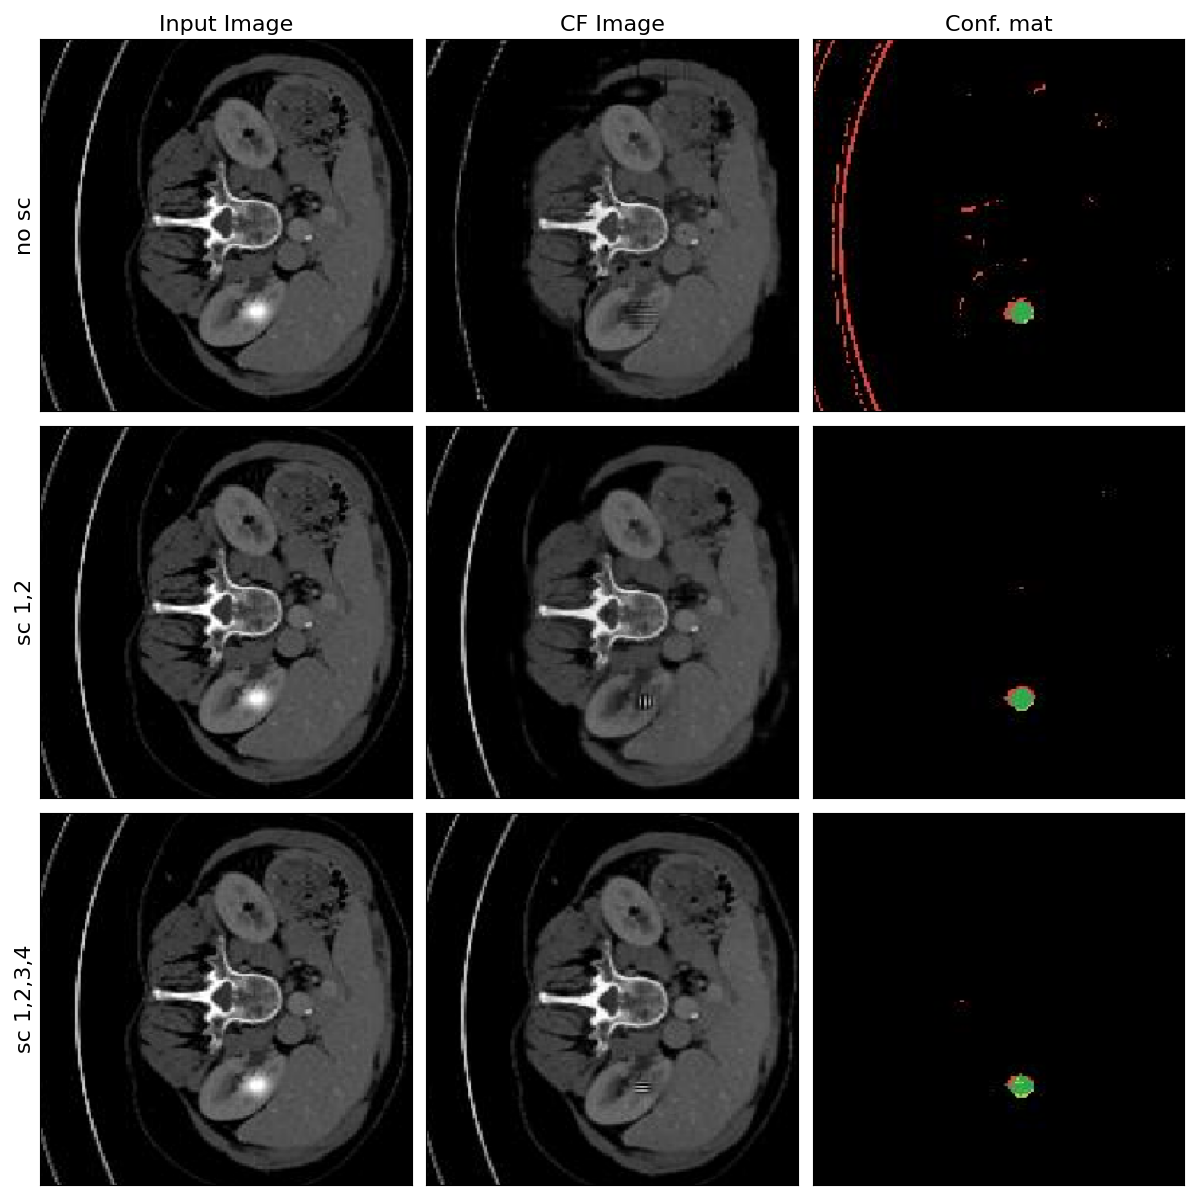

Moreover, COIN distinguishes itself by implementing a perturbation-based image generation within the GAN framework. The generator architecture is unique with slight modification of having a residual connection of the model’s input to the outputs. Instead of regenerating the complete image in the decoder from the latent variable, the generator is trained to produce only the perturbation map which is fused into the input image. Therefore, the explanation function is modified such that (X,δ)=G(E(X),δ)+X𝑋𝛿𝐺𝐸𝑋𝛿𝑋\mathscr{E}(X,\delta)=G(E(X),\delta)+Xscript_E ( italic_X , italic_δ ) = italic_G ( italic_E ( italic_X ) , italic_δ ) + italic_X. This technique contrasts with conventional counterfactual generation models [4, 17, 39], which typically reconstruct the entire image. While full reconstruction can be effective in some contexts, it often introduces artifacts — unintended alterations that can skew the classification model’s interpretation and analysis. The impact of perturbation-based architecture is illustrated in Appendix A Figure 4 and Table 3.

Additionally, in contrast to reported Singla et al. architecture, the skip-connections are integrated into the encoder-decoder model [30] together with perturbation-based approach. This enhancement facilitates the generation of more accurate perturbations, thereby improving reconstruction quality and preserving the original image details. The impact of skip-connections is showcased in Appendix A Figure 5 and Table 3. This approach is beneficial for WSSS as it ensures the generation of precise, artifact-free counterfactual explanations.

Appendix A

In this chapter, a detailed experimentation is given for the iterative improvements to the Singla et al.* method to obtain the COIN pipeline. Table 3 summarizes all the performed experiments and obtained metrics based on the TotalSegmentator and synthetic anomalies.

7.3 Original vs Perturbation-based generator

Refer to caption

Figure 4: Examples of images generated with original and perturbation-based Singla et al.* pipelines.

Within this experiment, the counterfactual explainer of Singla et al. is taken to validate the significant improvement employing the perturbation-based generation in terms of FID and IoU scores. The perturbation-based image generation generates much higher fidelity images. Instead of reconstructing the whole input image from scratch, the decoder learns to output only the changes needed to flip classifier decision. Figure 4 gives qualitative evaluation of the generated images following the two approaches.

7.4 Influence of skip connections on the generated images quality

Figure 5: Examples of images generated with and without skip-connections between encoder-decoder layers of the perturbation-based Singla et al.* pipeline.

In this experiment, the baseline of Singla et al. employing perturbation-based counterfactual generation from the previous section is taken to showcase the importance of skip connections in the generator network to mitigate drastic distortions of the input images. During the down-sampling process of the encoder, the information loss is inevitable, so reconstructing the counterfactual images with minimum perturbations becomes a challenge. Therefore, the skip connections between different down-sampling and up-sampling layers are gradually injected to show the improvements in terms of FID and IoU scores. The perturbation-based image generation leveraging skip connections results in less distorted images, hence, in lower FID score. Figure 5 gives qualitative evaluation of the generated images with and without adoption of skip-connections.